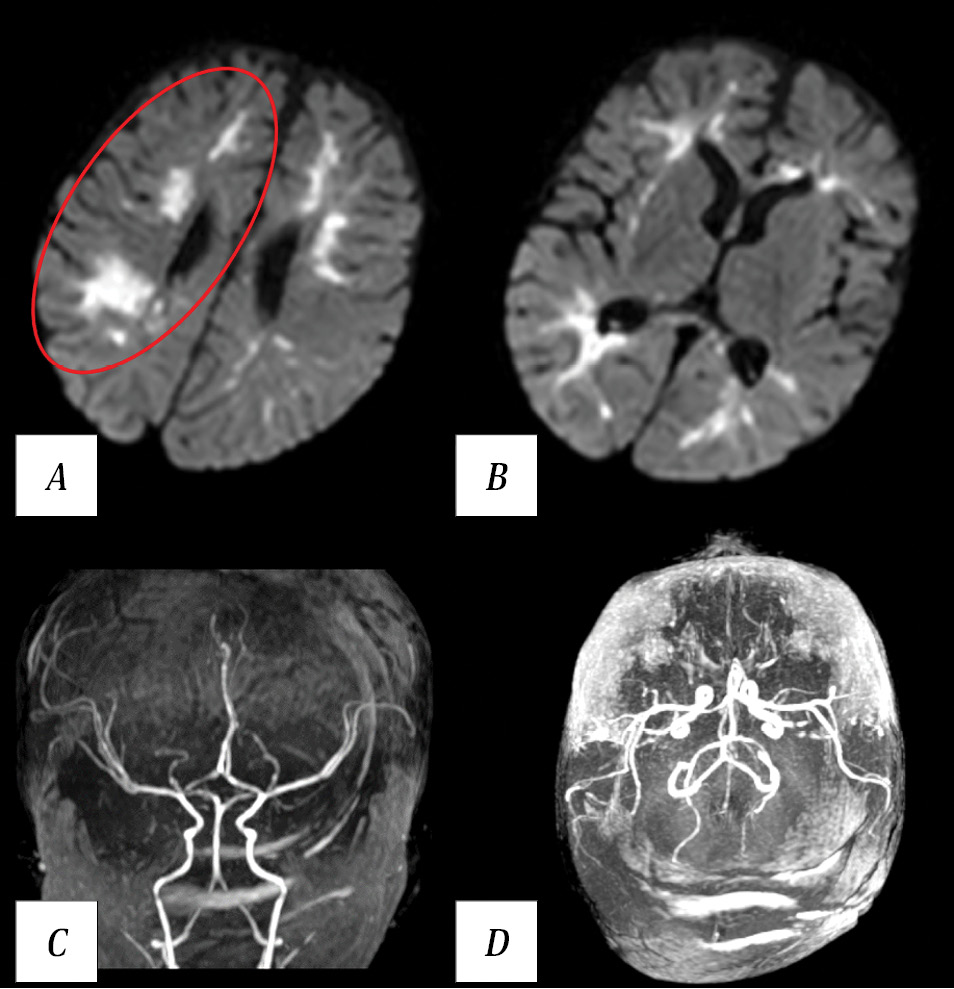

Brain MRI revealed watershed infarctions in both hemispheres (Fig. 5).

Fig. 5. Results of patient B. MRI on day 2 postoperatively.

A, B — brain MRI. DWI, axial plane. Watershed infarctions in both cerebral hemispheres. Red oval outlines the most extensive area in the right hemisphere; similar regions are observed in the left hemisphere. C, D — MR angiography, 3D reconstruction. Intracranial arterial blood flow remains intact.